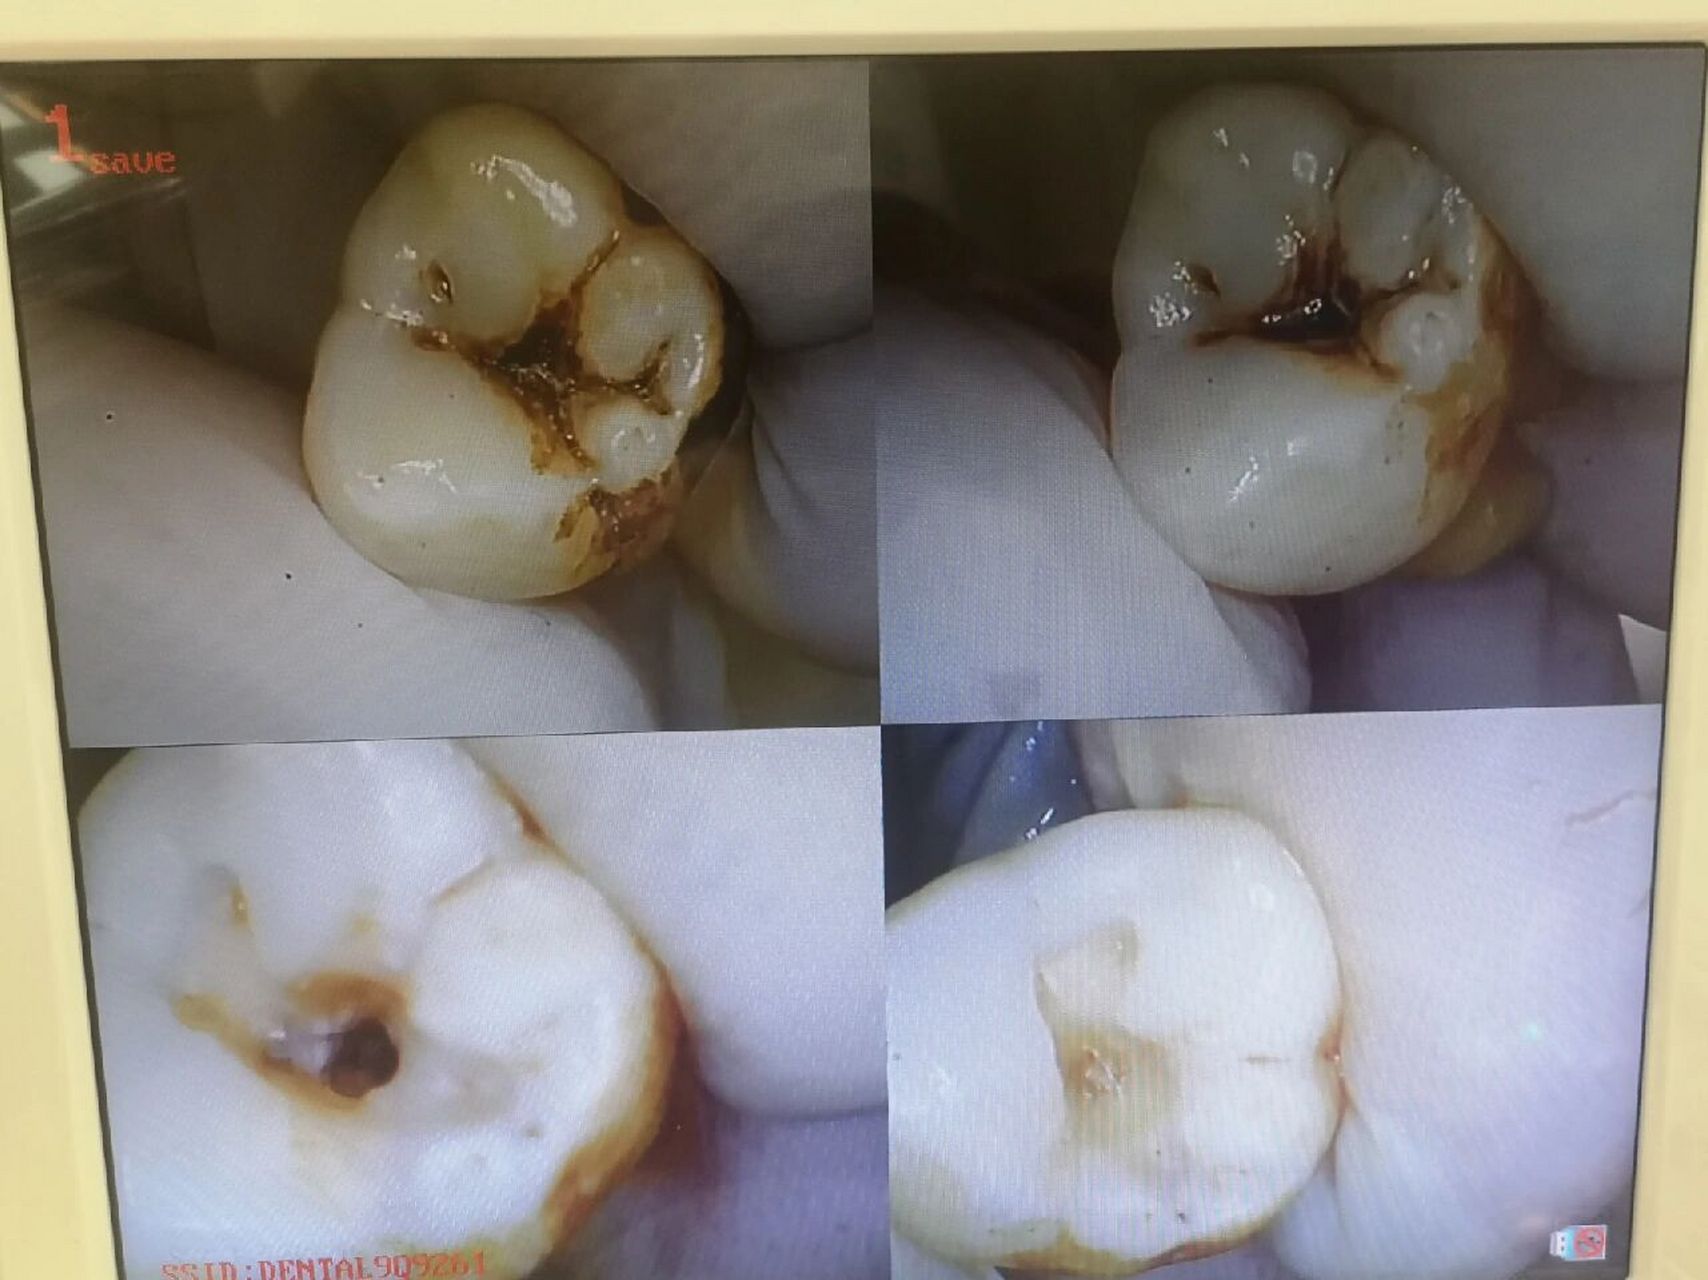

治疗中:34去龋后深达牙本质深层,近髓.33去龋后达牙本质浅层

看似中龋实际已深龋近髓